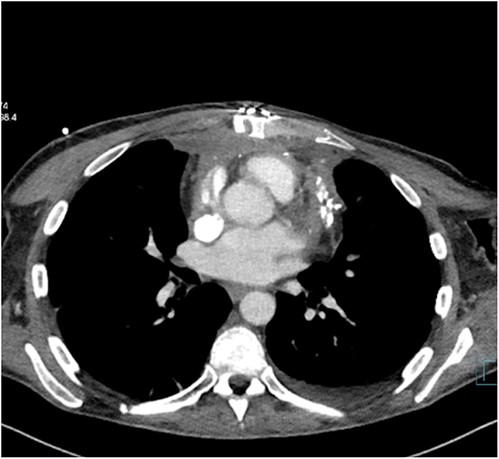

The patient was treated with anti-inflammatory drugs (colchicine), steroids and diuretics. Repeat MRI in 4 months’ time showed significant organized material within the pericardial space with associated pericardial thickening. There was both septal ‘bounce’/ ‘shudder’ and significant respirophasic septal shift on free-breathing, consistent with enhanced ventricular interdependence suggestive of constrictive physiology. CT scan revealed calcified and thickened pericardium (Figs 1 and 2).

Pericardectomy is the definitive treatment for symptomatic patients following cardiac surgery [4]. Prior coronary artery bypass graft (CABG) poses a higher risk with patent RItA graft travelling across beneath the sternum susceptible for injury during redo sternotomy. Other grafts are susceptible to injury at the time of dissection of the pericardium as SVG was grafted to OM1 and SVG was traveling in front of the right ventricle. CT scan and MRI are useful for diagnosis of the disease. We performed echocardiogram, CT scan and MRI for the confirmation of the diagnosis [5].